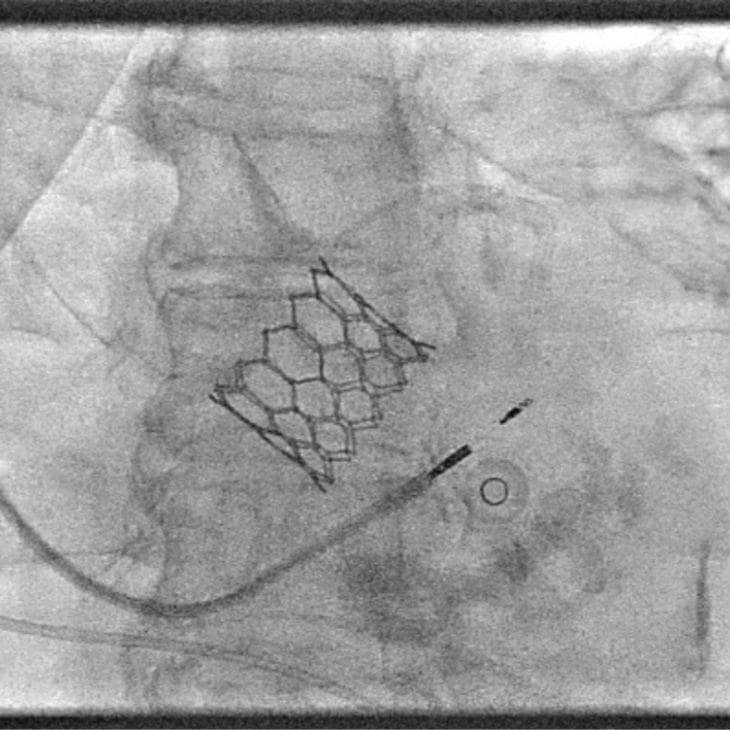

TAVI is a minimally invasive procedure to replace a narrowed aortic valve without open-heart surgery. Dr Sayan Sen offers expert transcatheter valve replacement from specialist cardiology centres in London for patients with severe aortic stenosis.

TAVI (Transcatheter Aortic Valve Implantation) is a procedure to replace a diseased aortic valve using a catheter-based approach, without the need for major surgery. It’s primarily used for patients with severe aortic stenosis.

A new valve is delivered through a blood vessel (usually via the groin) and positioned within the existing narrowed valve. Once in place, the replacement valve takes over blood flow control. TAVI offers a faster recovery, making it suitable for patients who may not be eligible for traditional open-heart valve surgery.